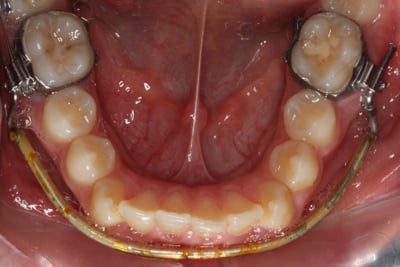

4. Greenfield Lip Bumper: występuje w dwóch formach – „normalnej” oraz „wysoko-kątowej”; skonstruowany ze stalowego drutu 0.045”, w odcinku przednim z tarczkami i zagięciem w kształcie odwróconej litery V w linii pośrodkowej w celu ominięcia wędzidełka języka oraz bocznie pętli stop o wymiarach 5x5mm odgiętych pod kątem 10o w kierunku policzkowym w dwóch wariantach:

Im przebieg łuku wargowego jest bliższy powierzchni okluzyjnej, tym widoczniejsza ekstruzja i nachylenie dystalne pierwszego trzonowca! Osłonięcie siekaczy, kłów i przedtrzonowców od działania warg i policzka umożliwia im wychylenie w kierunku wargowo-policzkowym.

I. Poziom I (normalna konfiguracja) – łuk wargowy przebiega okluzyjnie dzięki zastosowaniu normalnej pętli stop – pożądany w rzadkich sytuacjach, gdy siekacze są przechylone i/lub niewyrznięte i/lub pochylone mezjalnie pierwsze trzonowce. Może skutkować pochyleniem dystalnym i ekstruzją pierwszych trzonowców oraz wtłoczeniem drugich z powodu unoszenia przedniego odcinka łuku wargowego przez wargę dolną. W przypadku wystąpienia takiego zjawiska, łuk musi być usytuowany dowierzchołkowo w środkowej 1/3 powierzchni wargowej siekaczy i doprzednio od nich 2mm co 4-5 tygodni.

II. Poziom II (normalna konfiguracja) – łuk wargowy usytuowany 1,5-2mm poniżej i doprzednio od połączenia szkliwno-dziąsłowego – najczęściej spotykany w 80% przypadków. Pierwszy trzonowiec ulega ekstruzji w zdecydowanie mniejszym stopniu niż w typie I, pozycja siekaczy jest zachowana, przedtrzonowce mogą swobodnie przyjmować właściwą pozycję i przesuwać się dystalnie dzięki sile włókien międzyzębowych. Wytwarzana jest minimalna siła ekstruzyjna i przechylająca dystalnie zęby trzonowe oraz nieznaczne wychylenie siekaczy. Na pierwszych wizytach, wskutek zmiany położenia trzonowców, pozycja łuku wargowego musi być skorygowana, w przeciwnym wypadku łuk wargowy znajdzie się na poziomie I.

I. Pierwsza wizyta: lip bumper powinien zostać założony nieaktywny, nie dalej niż 1,5-2mm od powierzchni wargowej zębów, aby zapewnić pacjentowi maksymalny komfort.

II. Pierwsza wizyta kontrolna: aktywacja rozpoczęta niewielkim zwiększeniem rotacji na dystalnych końcach o 5-10o oraz poszerzeniem o 2-3mm w okolicy trzonowców, łuk wargowy powinien znajdować się w oddaleniu 1,5-2mm od zębów przednich i 2,5-3mm od przedtrzonowców